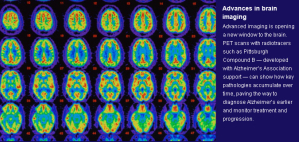

Alzheimer's and other dementias are caused by the buildup of microscopic clumps of a protein fragment called beta-amyloid and twisted strands of a protein called tau, which clog the space between brain cells and impede the transmission of information from cell to cell. Scientists say a key part of the future lies in identifying predictors of Alzheimer's — through memory and thinking tests and MRI scans — before symptoms occur.